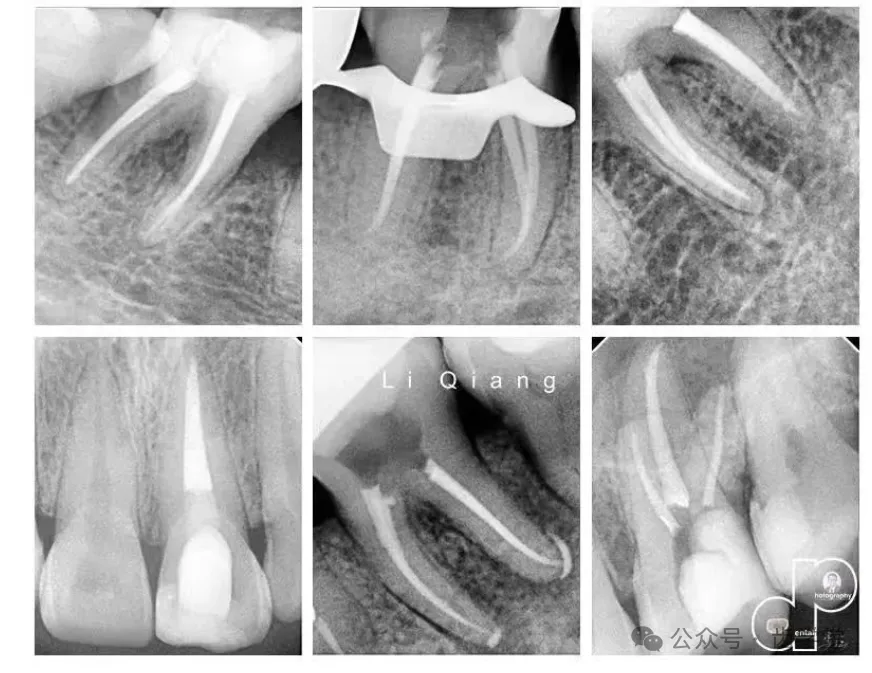

四、部分病例展示

五、李强近期部分影像: